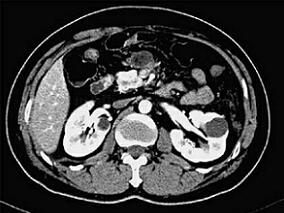

1小时条评论60岁女性,腹部包块2个月余。无恶心、腹胀及疼痛不适。腹部超声示腹膜后混合性包块,与胰尾分界不清。CT动态增强和病理结合,揭开这一多见于女性的肿瘤的面纱。 1.临床资料 病例4-1-35,女性,60岁,腹部包块2个月余。无恶心、腹胀及疼痛不适。腹部超声示腹膜后混...